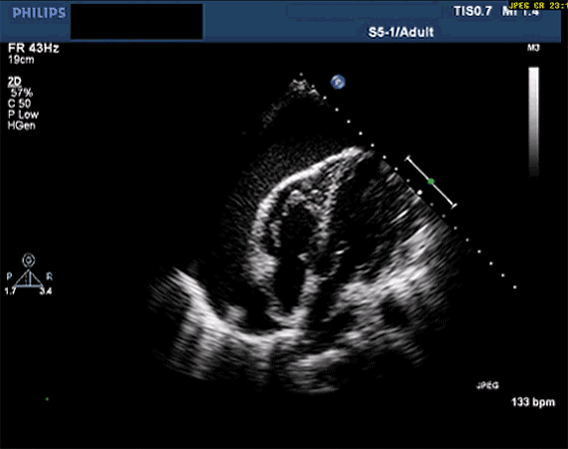

3. Ekokardiyografi (EKO) – Altın Standart 🚨

Yatak başında hızlı tanı imkânı sağlar (POCUS dahil)

Ekokardiyografide görülen temel bulgular:

- Perikardiyal efüzyon varlığı ve miktarı

- Sağ atriyum sistolik kollapsı

- Sağ ventrikül diyastolik kollapsı

- Plethoric (dilate, kollabe olmayan) VCI

- Kardiyak doluşun etkilenmesi

Ekokardiyografi sadece efüzyonu saptamakla kalmaz, aynı zamanda hemodinamik etkisini de gösterir.